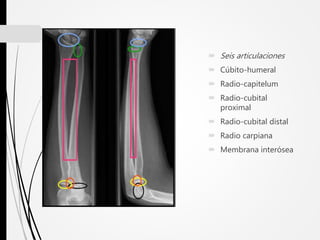

 Seis articulaciones

 Cúbito-humeral

 Radio-capitelum

 Radio-cubital

proximal

 Radio-cubital distal

 Radio carpiana

 Membrana interósea

 Seis articulaciones Cúbito-humeral  Radio-capitelum  Radio-cubital proximal  Radio-cubital distal  Radio carpiana  Membrana interósea